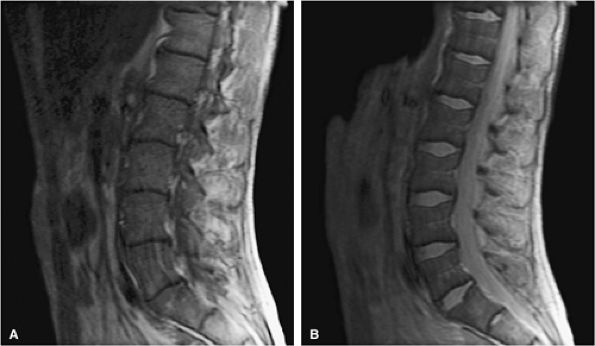

FIGURE 13.51 ● Diffuse marrow replacement with an epidural soft-tissue mass in a patient with multiple myeloma. (A) Sagittal T1-weighted image shows diffuse marrow replacement of the lumbar spine. The large epidural soft-tissue lesion causes a mass effect on the thecal sac (arrow). Myelomatous marrow infiltration is darker than the adjacent intervertebral disks. (B) Enhancement of the soft-tissue mass is shown on a sagittal fat-suppressed T1-weighted image after intravenous administration of gadolinium (arrow). (C) Diffuse marrow replacement is not well seen on the corresponding sagittal T2-weighted image.